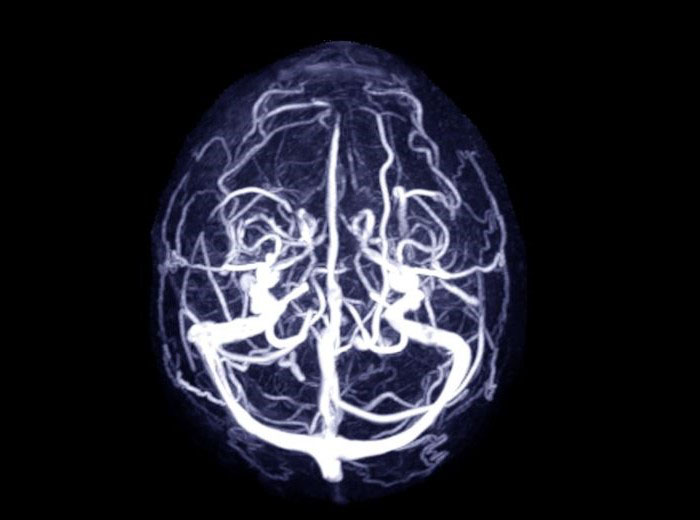

نوبت دهی ام آر وی یا ام آر ونوگرافی

ام آر ونوگرافی یا ام آر وی ، روش تصویربرداری است که برای رگ های خونی مغز استفاده می کند. این روش به پزشک اجازه کمک میکن...